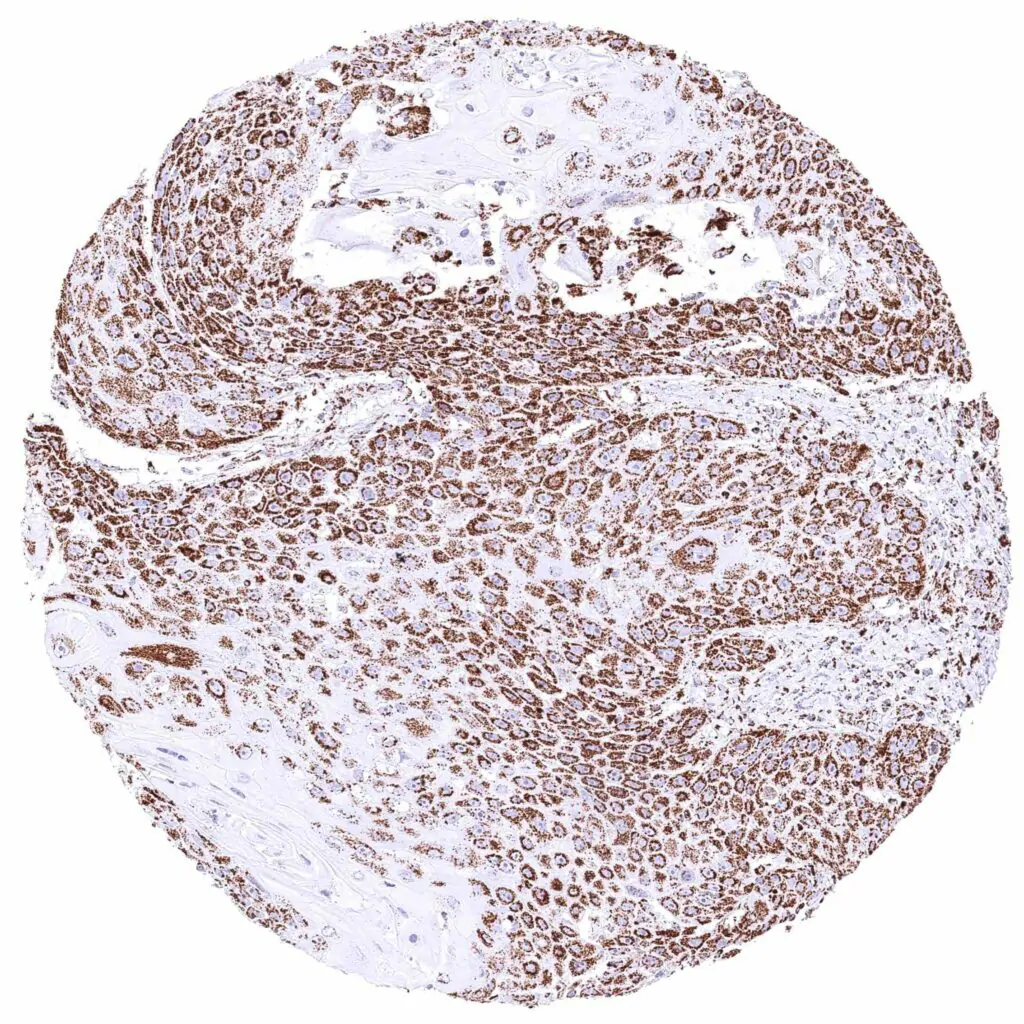

Breast – Invasive breast cancer of no special type (NST) with strong cytoplasmic ATP5J positivity of tumor cells.